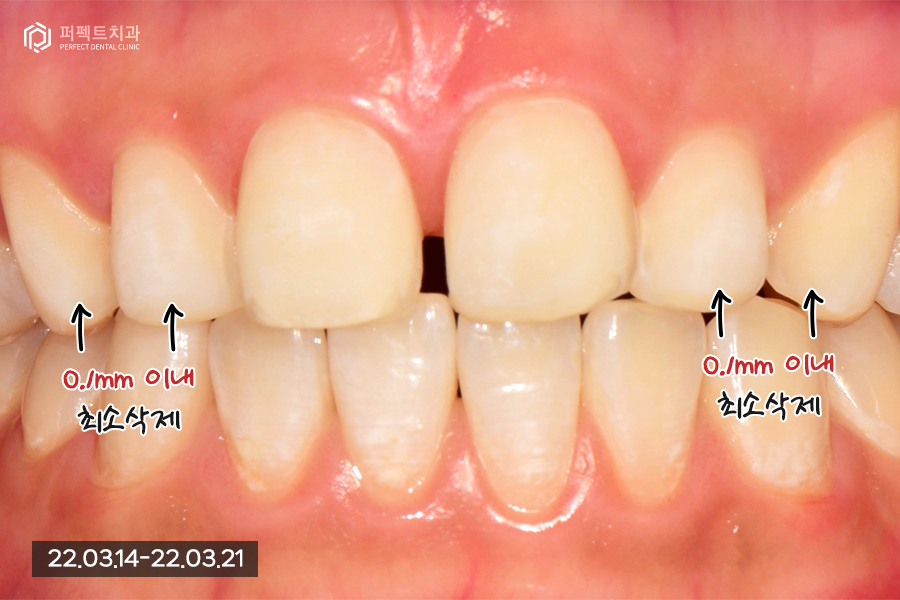

치아를 삭제한 후의 사진인데요. 두번째, 세번째 치아들은 뒤로 들어가있고 앞니가 튀어나온 상태이기 때문에 삭제할 필요가 없었습니다.

환자분은 아까 말씀드린 것처럼 앞니가 튀어나와 보여도 괜찮으니 최소삭제를 원하셨기 때문에 앞니는 0.2mm정도 최소삭제, 나머지 치아들은 0.1mm이내로 다듬기만 하였습니다.